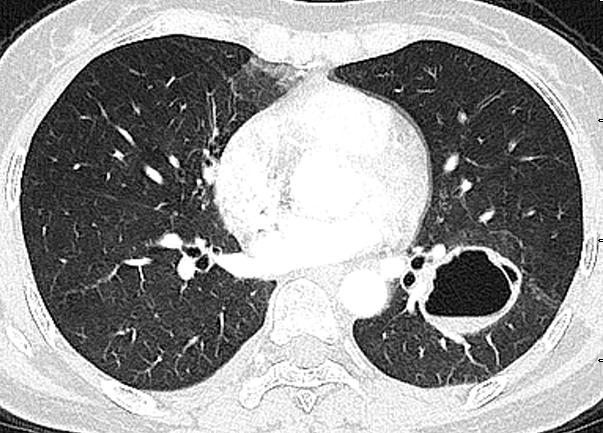

肺部感染可能出现的ct征象,你见过几个?(上)_支气管

气液平征03ct 可见半透明状密度增高影;主要见于病毒,支原体,真菌等